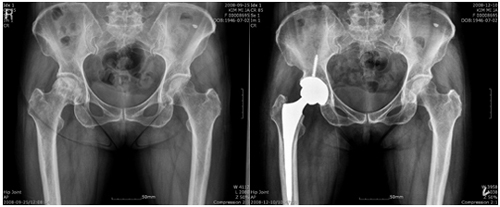

평소 사람들과 어울리기를 좋아해 자연스레 술자리도 잦은 평범한 직장인 강모(47세, 남)씨. 6개월 전부터 왼쪽 사타구니와 엉덩이 쪽으로 통증이 있었다고 한다. 시간이 지나면 낫겠지 하고 기다리다가 통증이 심해져서 찾아간 병원에서 뜻밖에 고관절 무혈성 괴사증이라는 진단을 받았다. 가정주부 권모(54세, 여)씨는 어릴 적부터 왼쪽 다리가 약간 짧고 움직임이 부자연스러웠다고 하는데 생활하는데 큰 불편함이나 통증이 없어서 별다른 걱정을 안 하고 살아왔다고 한다. 하지만 3년 전부터 서서히 통증이 심해졌고, 그녀는 집 가까운 병원에서 비구 이형성증에 의한 이차성 고관절 퇴행성 관절염으로 진단받았다. 두 사람 모두 병세가 심하여 말기라는 얘기를 들었고 결국 인공 고관절 치환술을 해야 한다는 전문의의 권유를 받았다. 아직은 비교적 젊은 축에 속한다고 생각한 그들은 인공 관절 수술을 해야 한다는 사실에 걱정이 앞서 잠시 망설였지만 결국 인공 고관절 치환술을 받았다. 지금은 많이 회복되어 거의 정상에 가까운 일상생활을 할 뿐만 아니라 자전거 타기를 하는데도 전혀 지장이 없을 정도로 관절 기능이 회복되었다. 인공 관절 치환술이 말기 관절염이나 무혈성 괴사증이 있을 경우 최선의 치료법이라는 것은 관심이 있는 사람들은 다 아는 사실이지만 인공 관절 수술을 하면 수명이 있고 또 고관절의 경우에는 탈구가 잘된다는 사실 때문에 수술을 피하게 되는 경우가 많이 있다. 강 모 씨나 권 모 씨처럼 나이가 아주 많지 않은 중년에는 더더욱 그러한 경향이 두드러진다. 인공 관절은 해가 갈수록 디자인이나 재질이 발전하고 있다. 무릎관절과 마찬가지로 고관절의 인공 관절도 나날이 발전하고 있는데 관절 접촉 부분을 세라믹으로 만들기 때문에 마모가 엄청나게 줄어들어 재수술이 필요한 확률을 낮추었으며 인공 관절의 수명도 그만큼 늘어나게 되었다. 세라믹이 인공 관절에 사용된 것은 어제 오늘의 일은 아니지만 과거의 세라믹은 마모는 잘 일어나지 않는 대신 세라믹이 깨지는 경우가 간혹 발생하여 환자와 의사를 곤혹스럽게 하는 경우가 있었기 때문에 사용을 꺼리는 의사들도 있었다. 최근에 개발한 세라믹 인공 관절은 4세대 세라믹을 이용한 것이다. 4세대 세라믹은 강도는 이전 세대보다 비슷하거나 더 강하면서도 잘 깨지지 않는다. 그러기 때문에 걱정 없이 사용할 수 있다. 그것뿐만이 아니다. 잘 깨지지 않기 때문에 인공 관절의 접촉 부분을 더 얇게 만들 수 있다. 이것은 기존에 쓰던 인공 대퇴 골두가 28mm의 지름을 가진 것에 비하여 36mm 정도의 지름으로 훨씬 더 큰 인공 골두를 사용할 수 있게 한다. 대퇴 골두가 커지면 움직임이 훨씬 자연스러우며 관절의 움직이는 범위도 커질 뿐만 아니라, 탈구가 잘 되지 않기 때문에 인공 고관절 수술 후에 관절이 빠지지 않을까 하는 걱정을 하나 덜 수 있다. 4세대 세라믹을 이용한 인공 고관절 수술, 세라믹이 깨지는 확률도 줄어들었고 큰 인공 대퇴 골두를 사용함으로써 관절의 움직임도 좋아지고 탈구도 예방할 수 있다고 하니 인공 관절의 진화는 대체 어디까지일까 지켜보는 것도 재미있는 일이 될 것 같다. 전재훈(연세사랑병원[강북점] 인공관절센터 과장). /OSEN=생활경제팀 osenlife@osen.co.kr 수술 전 후의 비교 사진.